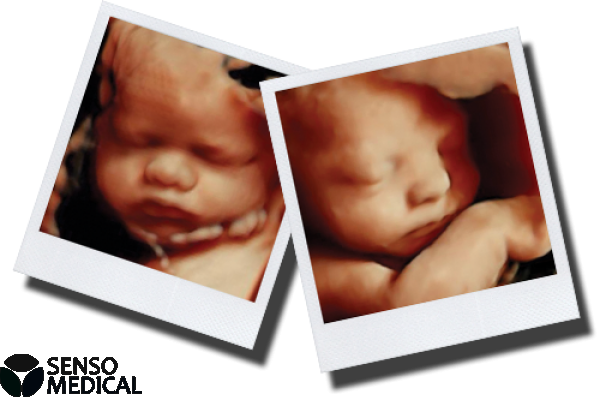

Ultrasonograf GE Voluson E8 Expert wersja oprogramowania BT13 (UISApp 13.0.6.254) 4D HDLive –

System Voluson E8 Expert to unikalne rozwiązanie w zakresie diagnostyki chorób kobiecych oferujące wysoką jakość obrazowania w trybach 2D i 3D/4D oraz uproszczone procedury usprawniające przepływ pracy i zapewniające najwyższą jakość badań. Więcej szczegółów, mniej wysiłku!